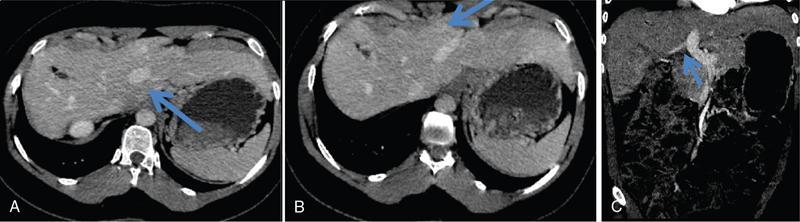

Ritu K. Kashikar, Shrinivas B. Desai, Payal Agrawal A spectrum of vascular variants can involve the liver. Both congenital and acquired anomalies can be seen. The abnormalities can involve the portal venous system, hepatic artery, hepatic veins or maybe the result of shunting between any of these vessels. Though not commonly encountered, familiarity with the pathogenesis and imaging features of these vascular entities can guide appropriate patient management. This chapter aims at classification of vascular pathologies of the liver (Table 9.12.1) with description of important entities. The umbilical vein accounts for approximately 80% of the afferent flow into the liver in utero. The umbilical vein joins the left portal vein, which in turn drains into the ductus venosus and carries blood to the inferior vena cava. The umbilical vein and ductus venosus start involuting at birth and typically close in the first week of life in term neonates (Fig. 9.12.1). Detailed embryology of the portal venous system has been discussed in previous chapters. The portal vein accounts for two-thirds of the hepatic blood supply. The distinctive feature of the portal vein is that it begins and ends in capillaries. The blood from the entire gastrointenstinal tract (except lower rectum), gallbladder, pancreas and spleen is carried via the portal vein to the liver. The hepatic arterial branches divide along the distribution of portal venous radicals and supply oxygenated blood to the sinusoids (Fig. 9.12.2). These include The dorsal and ventral limbs of the vitelline vein form the normal portal vein. Atrophy of the ventral limb occurs during embryogenesis. This maybe an incidental finding, though association with duodenal obstruction is seen in 50% cases. The aetiology of duodenal obstruction is often due to secondary causes such as duodenal stenosis, atresia, Ladd bands due to malrotation or annular pancreas. Associations include heterotaxy (polysplenia) and biliary atresia. Aberrant vessel may give an extrinsic impression on the high second portion of the duodenum on upper GI series. USG may show aberrant vessel in patients being scanned for other anomalies. The aberrant vessel is usually incidentally discovered intraoperatively during surgery for duodenal obstruction or malrotation. Hypoplasia or atresia of the portal vein may involve all or a portion of the portal vein. Atresia of a major branch is associated with absence of the corresponding hepatic lobe. Main portal vein hypoplasia or stenosis results in prehepatic portal hypertension and gastrointestinal hypertension (Flowchart 9.12.1). A portal vein smaller in calibre or as small as the adjacent hepatic artery is termed hypoplastic. The venous diameter in cases of hypoplasia is of 3 mm. Twenty-six per cent cases with biliary atresia have hypoplastic portal vein. TAPVR is a congenital cardiac malformation in which pulmonary veins instead of draining into left atrium during cardiac development, drain into the right atrium via an anomalous vein, resulting in right to left shunts. Types: In type 3 TAPVR an anomalous infradiaphragmatic vertical vein is formed by the confluence of pulmonary veins, typically through the oesophageal hiatus. Venous obstruction at the level of the diaphragm and accounts for the clinical presentation of pulmonary venous congestion and oedema. Early presentation (within 24–36 hours of life) included respiratory distress with cyanosis, tachypnea, and tachycardia. Features on X-ray include normal–sized heart with pulmonary interstitial oedema. One-third of patients have an additional complex cardiac anomaly and heterotaxy with right atrial isomerism. May show abnormal draining vein draining into the IVC or pulmonary vein. CT/MR venography allows accurate depiction of the anomaly. The pulmonary venous confluence drains to systemic veins below the diaphragm. The confluence is usually posterior to the left atrium and vertically oriented. From here, a descending vein passes through the oesophageal hiatus and most frequently drains into the connection in to ductus venosus, hepatic veins or inferior vena cava is not as frequent. Portosystemic shunts are classified into intrahepatic and extrahepatic. In the intrahepatic shunts, the shunt is at the level of PV branches after its division whereas in the extrahepatic shunts the anastomoses are between the tributaries of the portal or mesenteric system or main PV and a systemic vein (Flowchart 9.12.2). Abernethy malformation, also known as congenital extrahepatic portosystemic shunts (CEPS) is a rare clinical entity, in which portal blood is shunted partially or completely into the systemic circulation via an abnormal communication of the portal system with the systemic circulation. It results from persistence of embryonic vessels. The entity was named by John Abernethy in 1793. The embryological development of the portal vein occurs between the 4th and 10th weeks. The umbilical veins of chorionic origin, vitelline veins and the cardinal veins from the body of the embryo are the three paired venous systems seen in the embryo in the 4th week. Communications develop between the vitelline veins at 4 weeks, which anastomose to form a figure-of-eight configuration around the developing duodenum. Selective involution of these veins leads to the final configuration of the portal vein. Because the vena cava also has a complex development and is derived from several venous channels including the sinus venosus and a portion of the anastomosis between the right and left vitelline veins in the cranial part of the liver, it has been suggested that this may be the embryological basis of development of congenital extrahepatic portosystemic shunts. Various systems have been proposed for classification of Abernathy Syndrome: In this classification portal flow is classified as Patients with type A drainage show associated cardiac anomalies, while gastrointestinal bleeding is common in type C. In this system CEPS was classified into three types depending on the degree of severity of intrahepatic portal system hypoplasia in to mild, moderate and severe types. This system has therapeutic implications in providing information regarding acceptance of portal blood flow by the portal vasculature after shunt occlusion. CEPS may be asymptomatic well into adulthood and many authors have reported seeing adult patients presenting for the first time with clinical manifestations. Clinical features of portosystemic shunts may broadly be divided into: These include hepatopulmonary syndrome, metabolic dysfunction and hepatic encephalopathy. Patients with type 1 shunt have a female preponderance and often have concomitant congenital anomalies. These anomalies are less common in patients in type 2 shunts. Other anomalies have also been reported in patients with Abernethy malformation which include chromosomal anomalies such as Downs syndrome and structural anomalies of the heart, gastrointestinal, genitourinary, skeletal and vascular systems. Approximately half the patients of CEPS have nodular lesions of some sort in the liver (Flowchart 9.12.3). Nodular hepatic lesions in patients with congenital portosystemic shunts may be single or multiple. In order to establish a diagnosis of CEPS a communication between the portal and the systemic venous system, either before or after the formation of the PV by union of the SMV and SV has to demonstrated. Secondary causes of nonvisualization of the PV such as portal cavernoma or PV thrombus should be excluded. Patients with congenital portosystemic shunts do not have features of portal hypertension, such as splenomegaly, varices and collaterals. USG may demonstrate the shunt and show haemodynamics involved such as the magnitude and direction of flow. It may pick up congenital shunts preoperatively; however, it may not detect associated anomalies particularly of lung and heart. Smaller shunts, particularly type 1a may not be well picked up. Ultrasound may not fully characterize liver lesions seen in these patients. It is the modality of choice and can accurately diagnose the shunt and type and aids in management. Shunt is visualized as an abnormal communication between the portal venous and systemic circulation and is best depicted in the portal venous phase. CT also shows presence/absence of intrahepatic branches of portal vein. Evaluation of associated anomalies particularly in patients with congenital heart disease who require evaluation of pulmonary vasculature, or patients with suspected hepatopulmonary syndrome who require evaluation of the lungs can also be done with CT (Fig. 9.12.4 and Table 9.12.3). Another major advantage of CT is that it helps to detect and characterize hepatic lesions in these patients. It displays the arterial and venous anatomy, and provides an angiographic road map for surgical resection. Regenerative nodules are usually homogeneous with enhancement during arterial phase, on both CT, however without washout (Fig. 9.12.5). Rest of lesions show classic enhancement pattern as described in previous chapters. The imaging findings in patients with Abernethy malformation with hepatocellular carcinoma do not appear to be typical, that is hypervascularity on the arterial phase images with washout on delayed phase. Thus, patients who do not have typical findings of a benign lesion, that is lack of arterial enhancement, should be closely followed up or biopsied. Disadvantages of an MRI include longer periods of sedation which is a disadvantage in patients with CEPS who may be very young, very hypoxemic or encephalopathic. MRI also has lower spatial resolution than CT and may not show small intrahepatic portal venous radicles in type 2 patients. MRI can otherwise show all abnormalities seen on CT. Advantages of MRI using hepatobiliary contrast agents are in the characterization of hepatic nodules and for follow-up. MRI does not expose the patients to ionizing radiation. Patients with no symptoms, those with mild metabolic abnormalities and with liver nodules should be followed up with ultrasound and biochemistry. Patients with portosystemic encephalopathy, liver dysfunction or those with shunt ratio >60% should be treated according to type of shunt. Patients with type 1 shunts should be transplanted. Patients with type 2 shunts should be treated with shunt closure – either via embolization or surgical. Liver transplantation is considered when medical and surgical methods fail especially in patients with complications. Intrahepatic portosystemic shunts are rare. They may be congenital or result from trauma or portal hypertension. They develop due to persistent communications between vitelline and umbilical systems. These are communications between the branches of the PV and inferior vena cava (IVC). Park et al. classified these 1990 in four types. Type 5 was added later, these are classified in Table 9.12.4. Type 2 shunt with or without a focal varix is the most common type reported. Another classification system is proposed by Kanasawa et al. based on correlation with severity of portal hypoplasia (mild, moderate and severe) with portal venous pressure, histopathological findings, postoperative portal venous flow and hepatic regeneration. Associated anomalies such as cardiovascular, hepatobiliary, urogenital and gastrointenstinal can be seen. Complications such as portopulmonary hypertension are seen in 13%–66% children. As a consequence of long-term shunting, hepatic encephalopathy, and hepatopulmonary syndrome are the most common symptoms. Tumours such as FNH and regenerating nodular hyperplasia can be seen. These shunts may close spontaneously within the first 2 years of life or may remain asymptomatic and undetected for several years. When chronic shunting persists into adulthood, patients most often present with encephalopathy. The feeding (afferent) and draining (efferent) vessels of the shunt appear as enlarged, tubular, anechoic structures that are contiguous with the portal and hepatic veins. Antegrade flow is seen on colour Doppler images. Focal varix if present appears as an abnormal, rounded cystic structure with turbulent flow. Doppler study can also calculate the shunt ratio (total blood flow volume in the shunt divided by the blood flow in the portal vein). Shunt ratios greater than 60% should be corrected to prevent complications. Loss of normal undulating waveform of afferent portal vein branch with increased flow velocity and phasic waveforms owing to transmitted cardiac pulsations can be seen. The efferent hepatic vein branch of the shunt can show continuous flow with flattening of the Doppler waveform due to increased portal venous inflow. Communication between intrahepatic portal venous and peripheral hepatic venous radicals can be demonstrated easily on both contrast-enhanced CT and MRI. Similar to extrahepatic shunts CT is preferred over MRI in documentation of shunts. The afferent portal vein branch and the efferent hepatic vein branch are enlarged. Venous varices can be seen. The draining hepatic vein branch opacifies earlier than other hepatic veins (Fig. 9.12.6 and Table 9.12.5). The liver may show fatty degeneration and atrophy, but when the anomaly is corrected, fatty replacement disappears and liver size increases. Conservative medical therapy including restriction of protein and ingestion of lactulose. Symptomatic intrahepatic portosystemic shunts can be managed conservatively or with transcatheter embolization, surgical ligation or partial hepatectomy. The connection between the left umbilical vein and right hepatocardiac vein (future IVC) in the foetal circulation is called ductus venosus. This vessel is responsible for carrying nutrient-rich blood from placenta to the right atrium directly by bypassing the sinusoidal plexus of the liver. The umbilical vein and ductus venosus close at birth and form the ligamentum teres and ligamentum venous, respectively. The time interval following birth for closure of ductus venosus is variable ranging from few minutes after birth to 18 days in term neonates and as late as 37 days in premature infants. Patent ductus venosus is an intrahepatic portocaval shunt causing partial or complete diversion of portal blood to the systemic circulation and may present with hyperammonemia. Patent ductus venosus is seen on Doppler sonography as a vascular tubular structure in the left lobe of the liver, continuing from the umbilical vein and connecting the portal vein to the inferior vena cava. The foetal ductus venosus show waveforms similar to IVC corresponding to the cardiac cycle with a systolic and diastolic component. This diphasic waveform is seen in preterm and term infants and becomes monophasic as ductus closes. CT and MRI also accurately detect the shunt and patency. Associated hepatic lesions seen in patients with portosystemic shunts can be diagnosed and characterized better. Treatment (closure) is recommended in cases with complications or to prevent complications if the shunts persisted beyond 2 years of age. Shunt closure can be performed surgically or endoscopically. The complex nature of the shunt can pose problems during surgical closure. Transvenous and balloon occlusion have been done successfully. Occlusion of portal vein can occur due to a variety of conditions. The aetiologies of portal venous thrombosis in the neonatal age group include umbilical vein catheterization, omphalitis, dehydration or neonatal sepsis. Older children develop occlusion secondary to intraabdominal infections and portal hypertension. Other aetiological factors include prothrombotic states such as hereditary deficiency of protein C or protein S and factor V Leiden deficiency, vascular injury, trauma, stasis and congenital anomalies such as webs. Acute portal vein thrombosis can be asymptomatic, or the patient may present with abdominal pain, ascites or fever. Chronic portal vein thrombosis presents as ascites, encephalopathy, varices and upper gastrointestinal bleeding. Acute thrombus appears hypoechoic filling defect on USG with absent flow on Doppler. There is distension of the thrombosed vein (Fig. 9.12.7). CT and MRI with contrast will detect filling defect in the vein with distension. T2W1 images may show absence of flow void. Acute thrombus may appear hyperintense on T1W1 images. Tumour thrombus reveals signal similar to tumour on all sequences with diffusion restriction (Fig. 9.12.8). Chronic thrombus may present as eccentric filling defect, attenuation of vein or less commonly calcification of vessel wall. Collaterals are often seen in chronic portal vein thrombosis. Treatment usually involves combination of anticoagulation and intervention depending on age of thrombus. An acute portal venous thrombus may undergo partial or complete spontaneous resolution. The commonest cause of paediatric portal hypertension in the developing world is extrahepatic portal vein obstruction (EHPVO). It is also the second most common cause of portal hypertension in the western world. EHPVO is a condition characterized by obstruction of the extrahepatic portal vein (as the name suggests) with or without associated involvement of the intrahepatic branches, splenic vein (SV) or superior mesenteric vein (SMV). The hallmark of this chronic longstanding condition is carvernomatous transformation of the portal vein. Acute and chronic portal vein thromboses occurring in the setting of liver cirrhosis or HCC are not included in this disorder. EHPVO is an important cause of noncirrhotic portal hypertension with preserved liver structure and function till late in course of the disease. Proposed aetiologies include infection or prothrombotic event occurring early in life (in genetically predisposed individuals), leading to portal venous occlusion (Table 9.12.6).